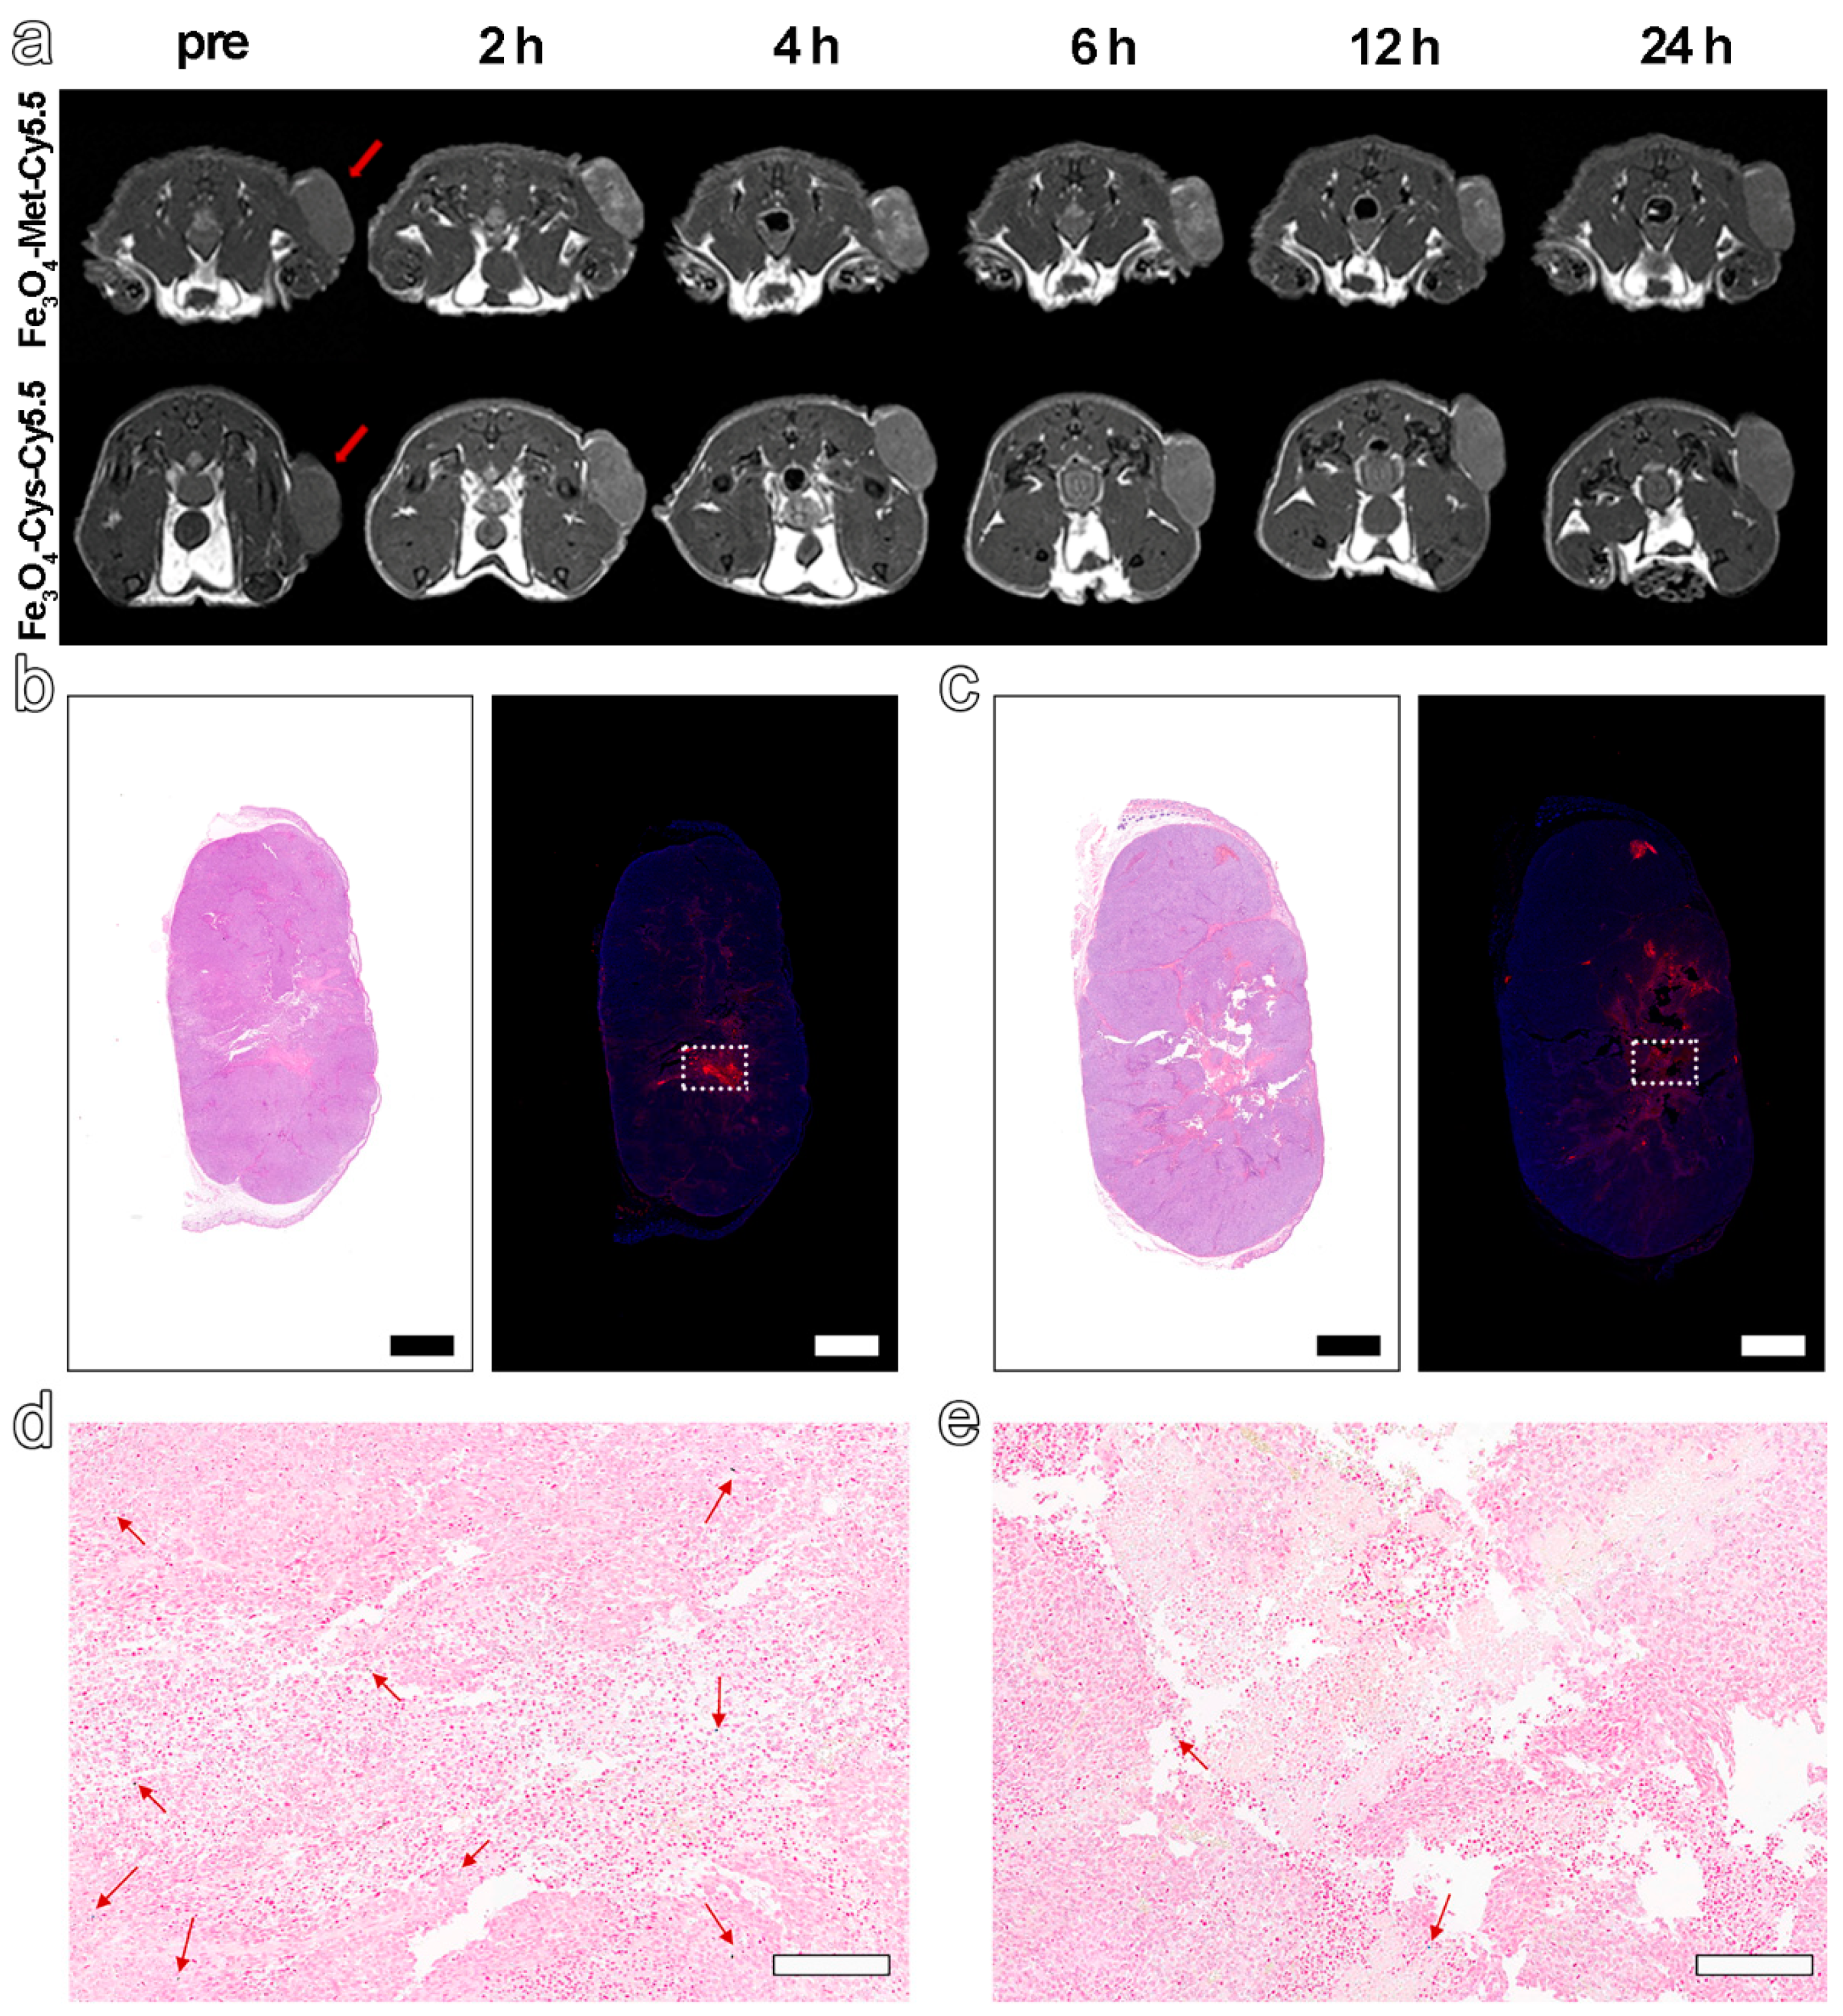

Based on the excellent hypoxia sensitivity in vitro, the nanoprobes were further intravenously injected into MCF-7 tumor-bearing mice (5.6 mg Fe kg−1 bodyweight) to explore the ability to detect hypoxia in vivo via MRI. The T1-weighted MR images at different time points before (pre) and post-injection (2 h, 4 h, 6 h, 12 h, 24 h) were collected by 3 T MRI apparatus. The results in Figure 4a displayed an obvious brightening trend in the signal arising from the tumor site for both groups and up to 6 h post-injection. However, from 6 to 24 h after injection, a decreasing signal tendency was identified for both groups. Furthermore, the normalized ratio of signal intensity arising from the tumor site to that of normal muscle (T/N) in Figure 4a and Figure S7 clearly exhibited that Fe3O4-Met-Cy5.5 could provide a higher contrast than that of Fe3O4-Cys-Cy5.5 (1.39 vs. 1.18 at 6 h post-injection). Anyway, the trend of the MRI signals in the two groups had statistically significant differences at 2, 4, 6, and 12 h post-injection (Figure S8a). Based on the above results, the ability of Fe3O4-Met-Cy5.5 and Fe3O4-Cys-Cy5.5 to target the tumors through the EPR effect can presumably be considered similar, due to their similar sizes and surface modifications. Therefore, this higher tumor contrast was assumed to originate from the hypoxic condition of the tumor, which might lie in the specific accumulation of metronidazole moieties. This conjecture is reasonable as the central area of the tumor site in Figure 4a, which preferred a hypoxic state, due to the limited oxygen supply capacity, and was visibly brighter than the surrounding region of the tumor treated with Fe3O4-Met-Cy5.5. To verify this assumption, the tumors were harvested and subjected to H&E and immunofluorescence staining of the HIF-1α antibody. As illustrated in Figure 4b,c, areas of tumor necrosis in H&E staining and hypoxic regions in HIF-1α staining were identified for both groups. More importantly, the distribution of the red fluorescence of HIF-1α, given in Figure 4b, was generally consistent with the brightening area of Fe3O4-Met-Cy5.5-treated group, verifying that our previous assumption was valid. In addition, Prussian blue staining of the hypoxic regions from the adjacent slices showed that both nanoprobes still had retention in the tumor regions after injection for 24 h (Figure 4d,e).

Figure 4. (a) T1-weighted MRI of tumor-bearing mice within 24 h, before and after injection with Fe3O4-Met-Cy5.5 or Fe3O4-Cys-Cy5.5. H&E staining (left) and immunofluorescence staining (right) for tumors of mice injected with Fe3O4-Met-Cy5.5 (b) or Fe3O4-Cys-Cy5.5 (c) (scale bars represent 1000 μm). Prussian blue staining of hypoxic area (dashed area on immunofluorescence staining images) in the tumors of mice treated with Fe3O4-Met-Cy5.5 (d) or Fe3O4-Cys-Cy5.5 (e) (scale bars represent 200 μm).